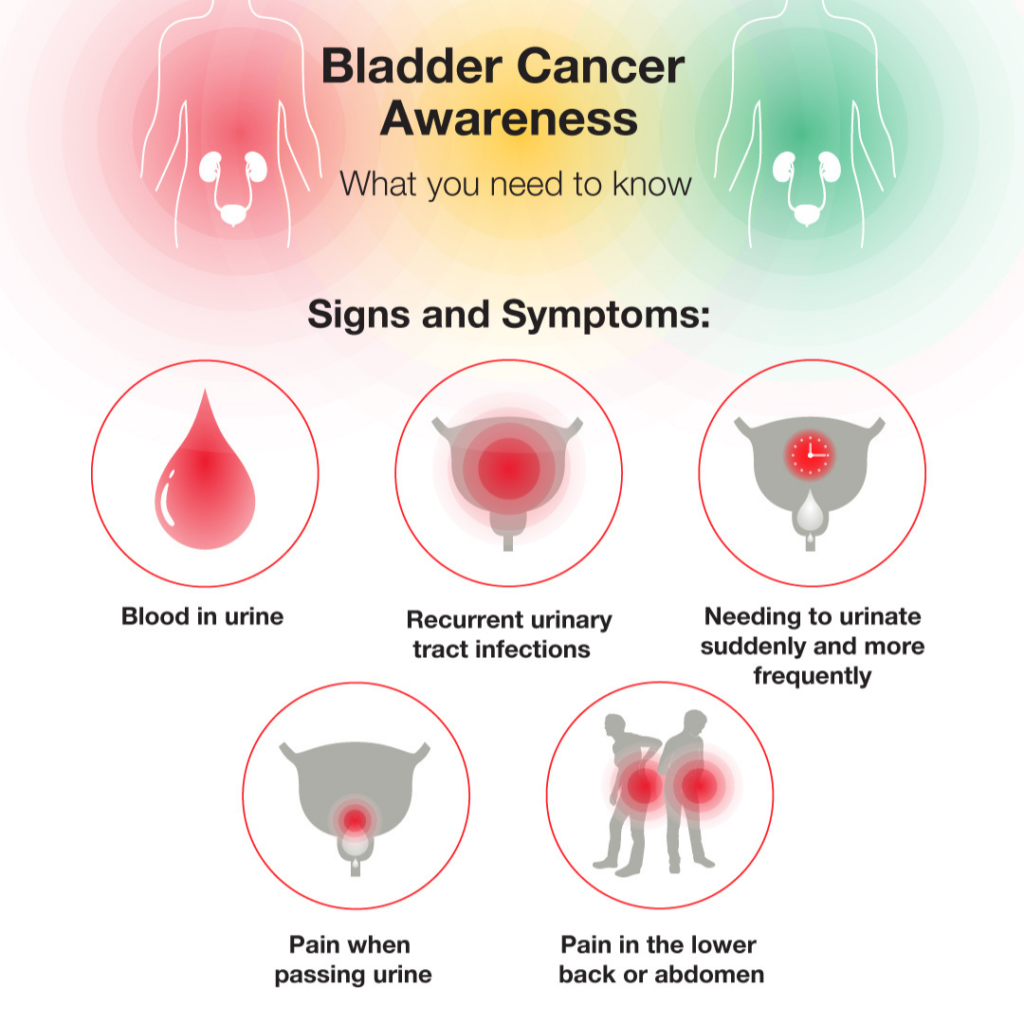

what is the most common sign of bladder cancer Updated

what are the symptoms of bladder cancer in a male Updated

Bladder Cancer: Symptoms and Treatment – Healthsoul

What Are The Signs Of Bladder Cancer In Males : How We Diagnose Bladder …

What Are The Signs Of Bladder Cancer In Females / Bladder cancer and …

Bladder Cancer. Signs, Symptoms and Treatment of Bladder Cancer